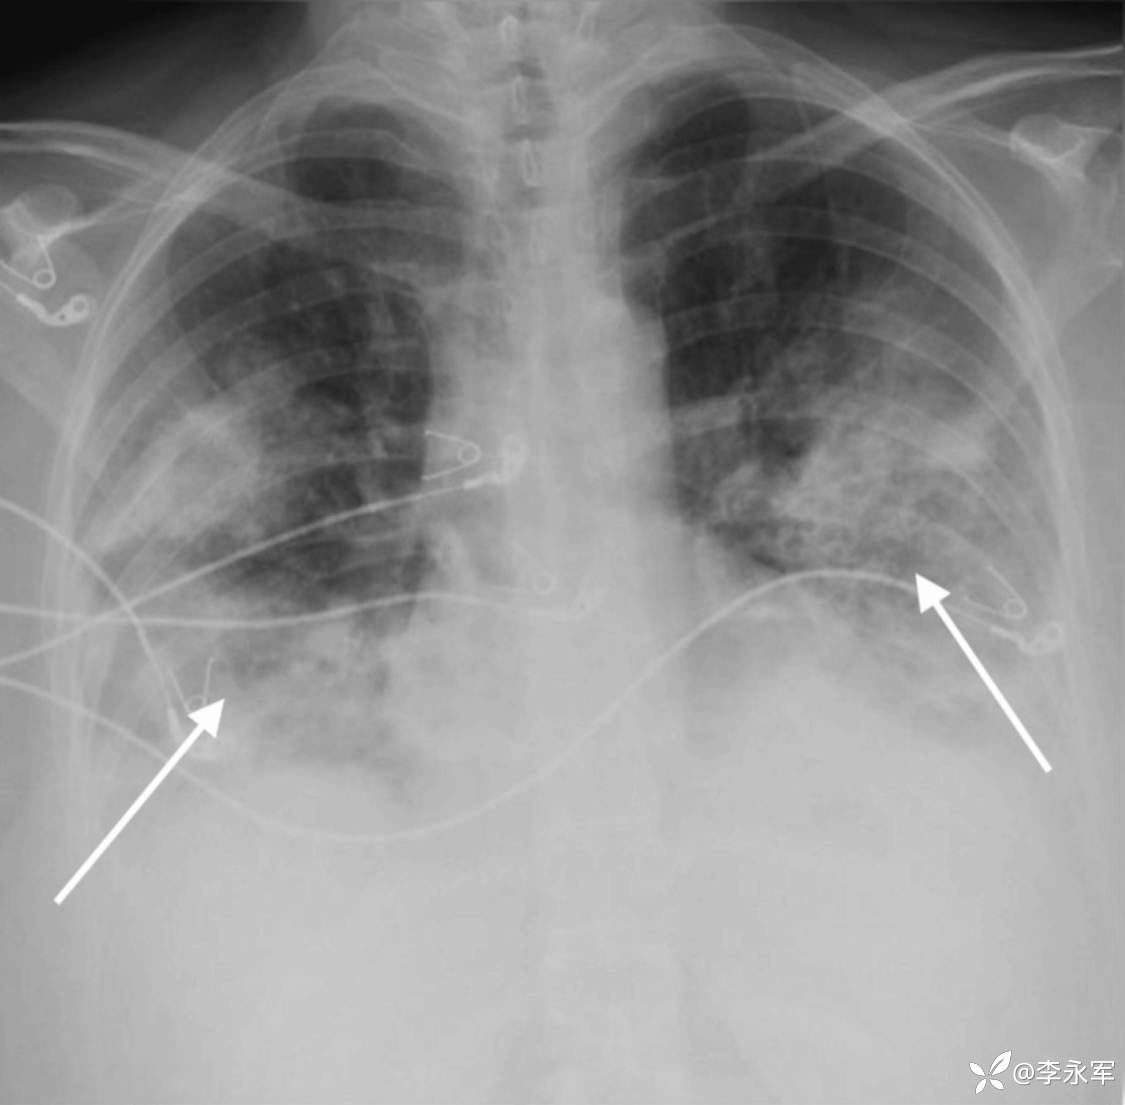

请传染病科会诊,并开始使用广谱抗生素(头孢曲松、左氧氟沙星和替考拉宁)。继续使用奥司他韦。患者被收治入 ICU 进行监测和治疗。在接下来的 24 小时内,病情恶化,胸部 X 光片显示加重(图 4),需要插管和机械通气。

图 4:入院 24 小时后胸部 X 光片